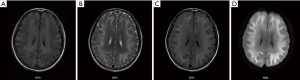

The patient was required to continue receiving treatment after discharge and also received regular outpatient visits. She took her medications every day and received hyperbaric oxygen treatment once a week. We performed another cranial MRI (Figure 2) after a month of treatment. Compared with her pre-treatment MRI, these results indicated that the demyelination had slightly improved in the corresponding brain regions.

The patient’s MRI showed extensive white matter signal abnormalities, particularly in the frontal lobe, temporal lobe, basal ganglia, before treatment. This indicated more extensive injuries to these regions (Figure 3). Studies have shown that the frontal lobe, the anterior region of the cerebral hemispheres, controls movement, language, intelligence, emotional regulation, et cetera (22). The temporal lobe, located beneath the lateral fissure of each cerebral hemisphere is involved with emotion, auditory processing, remembering visuospatial information, et cetera (22,23). The parietal lobe, located at the posterior top of the cerebral hemispheres, controls sensory skills and is important in reading, et cetera (24). The functions of these brain regions are consistent with the cognitive dysfunction that the patient exhibited. Compared with her pre-treatment MRI, an MRI taken after one month of treatment showed that the white matter signal abnormalities in these regions had reduced. The size of the areas that showed abnormalities had also decreased. These changes aligned with assessments of the patient’s symptoms and cognitive function, demonstrating that her treatment was effective.